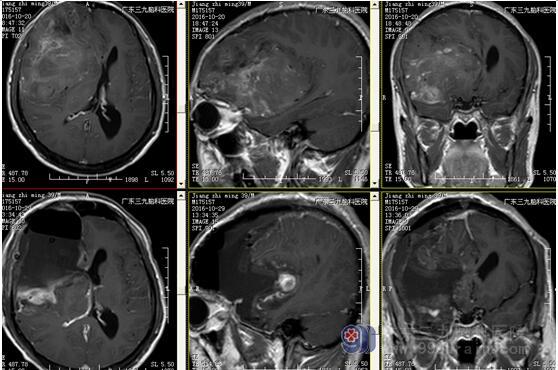

图3:术前磁共振显示肿瘤位置及大小约10.8×8.6×8.7cm

图5:术前、术后磁共振对比显示肿瘤全切

少突胶质细胞瘤无包膜,与周围脑组织界限清晰,50%-80%病例出现钙化,可散在或融合成较大的钙化小体,弯曲条带状钙化为其特征性表现,但广泛钙化罕见。本例肿瘤巨大(范围约为10.8×8.6×8.7cm),CT示斑片状低密度影及条带状典型高密度钙化影,病灶内及边缘示多发迂曲血管影沿钙化斑块走行,强化后呈轻度不均匀异常强化影,均符合少突胶质瘤典型影像学改变。